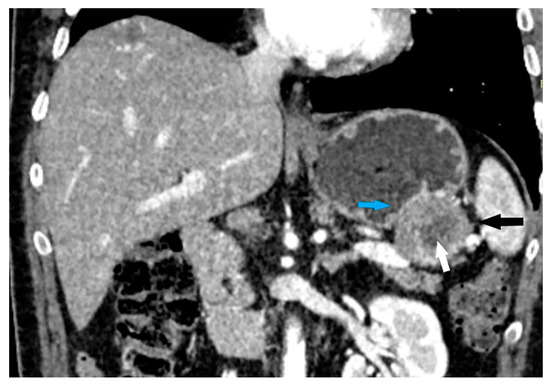

- The presence of visible enlarged vascular structures draining/feeding the tumor (EFDV “enlarged feeding or draining vessel”) (Figure 6);